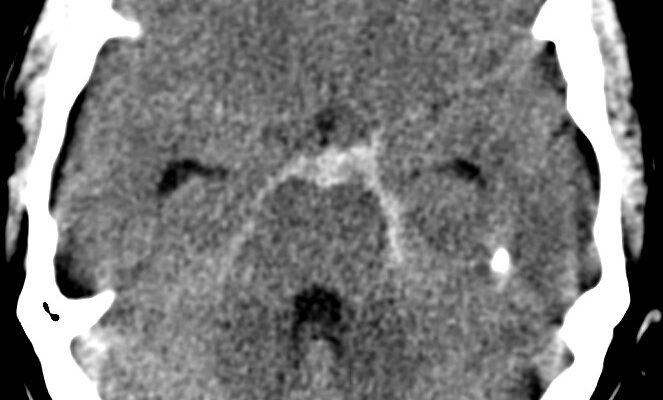

Що таке субарахноїдальний крововилив?

Субарахноїдальний крововилив — це кровотеча у простір між мозком і тканиною, яка його покриває. Цей простір називається субарахноїдальним простором. І хоча цей термін може здатися технічним, реальність така, що його наслідки можуть бути справді значущими для кожного.

Переважно причинами СК є розрив аневризми чи травми голови. Уявіть собі маленький мішочок, наповнений кров’ю, що вибухає. Ось так працює аневризма! Хоча й не завжди головна причина… Травма може також стати винуватцем, залишаючи мозок вразливим.